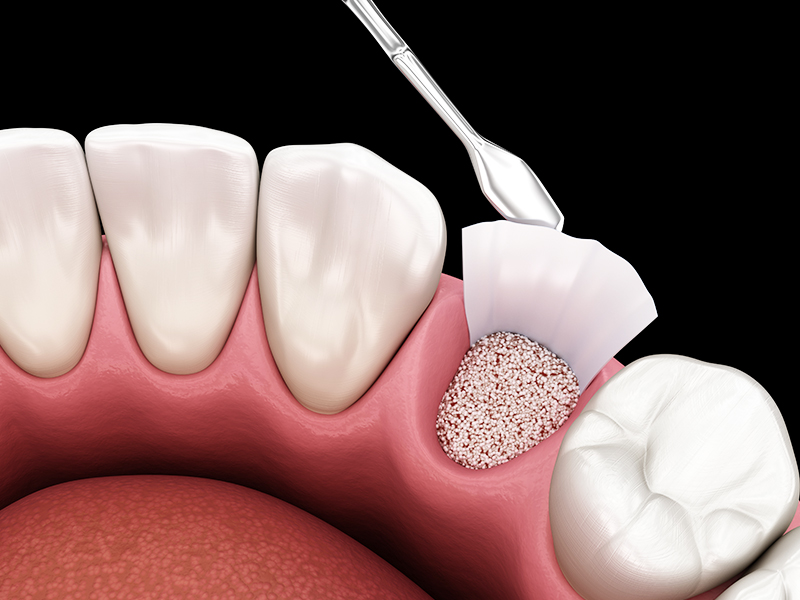

GBR(骨誘導再生法)は、損傷した顎の骨を再生するための骨造成の一つです。歯周病などで骨が失われた部位に、新しい骨を形成することができます。

まず歯ぐきを切開し、骨を再生させたい部分に骨補填材や自家骨(患者自身の骨)を注入します。その後、チタンメッシュや「メンブレン」と呼ばれる人工膜でこの領域を覆うことで、骨再生を阻害する繊維芽細胞の侵入を防ぎ、骨の再生を促します。